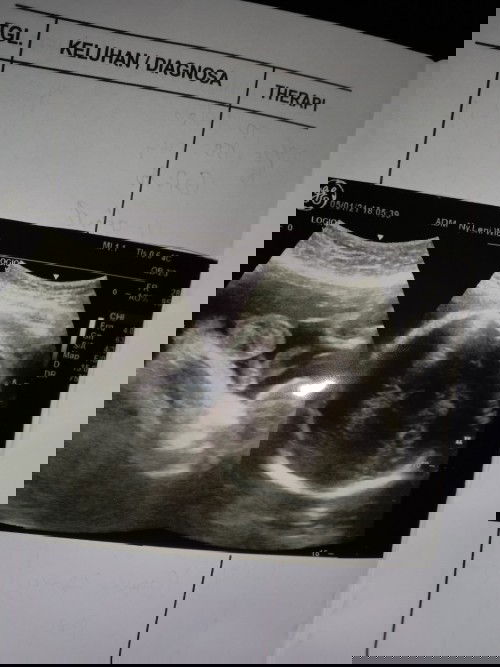

Bunda2 saya mau tanya? Siapa yg udah USG pakai yg 2D, akurat GK ya di USG 2 X cewe, lahir nya cowo

lebih akurat yang 4D bun. lebih jelas.. mungkin waktu itu si monasnya utun ketutupan sama ari2 makanya dokter bilang cewe bun, dan yang lahir cowo